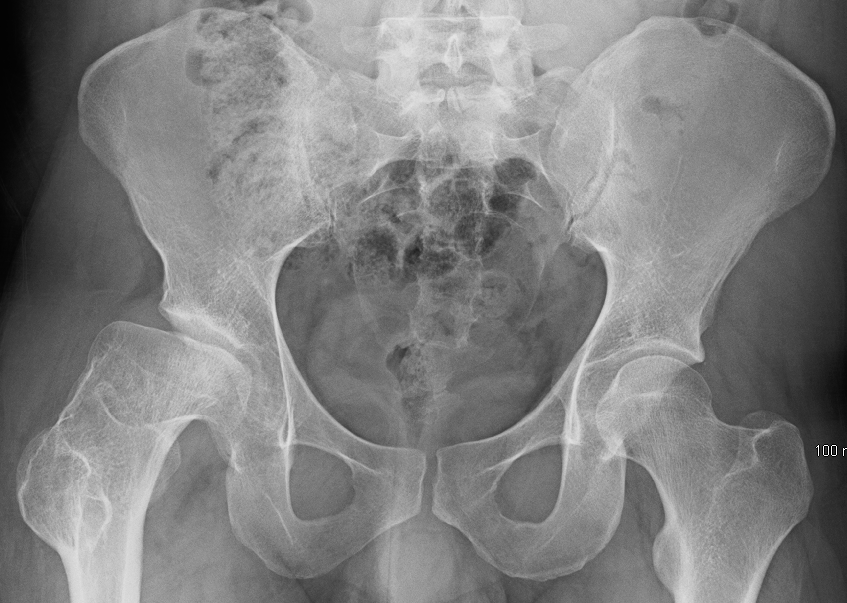

Хвороба Пертеса — загадкове захворювання, яке впливає на дітей, але наслідки його можуть тягтися впродовж усього життя. Це стан, що зачіпає тазостегновий суглоб, і призводить до порушення кровопостачання головки стегнової кістки. Як результат, кістка починає розпадатися. Звучить страшнувато, чи не так?

Хвороба Пертеса, яку ще називають аваскулярним некрозом, є розладом, що зазвичай діагностується у дітей віком від 4 до 10 років. І хоча вона стосується лише одного суглобу, її наслідки можуть бути відчутними протягом багатьох років і навіть після одужання.

- Окостеніння: головка стегнової кістки може змінювати форму, стаючи сплощеною або деформованою.